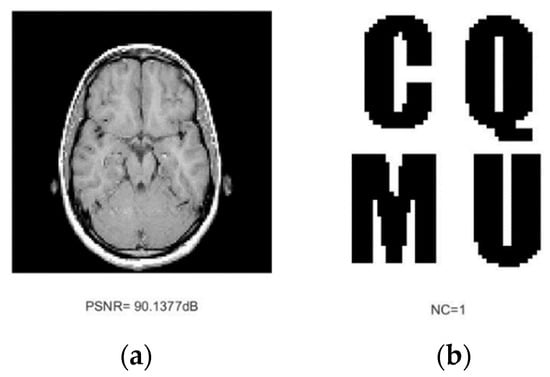

| Medical image A | 90.1377 | 1.0000 | 56.9175 | 1.0000 | 12.9247 | 0.9753 | 18.7664 | 0.9377 | 13.59 | 0.9377 |